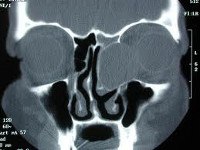

Рентгенологическое исследование при мукоцеле лобной пазухи определяет увеличение размеров пазухи, растяжение ее дна, уменьшение прозрачности. Возможно выпячивание перегородки между лобными пазухами в здоровую сторону. Прерывистость контуров лобной пазухи может указывать на наличие фистулы. Более точным и информативным исследованием является КТ лобной пазухи. Может применяться УЗИ и МРТ околоносовых пазух. В некоторых случаях для определения воздушности лобной пазухи проводится диафаноскопию. При затруднениях в диагностике мукоцеле лобной пазухи показана диагностическая пункция. Для определения проходимости лобно-носового канала производят зондирование лобной пазухи зондом Лансберга.